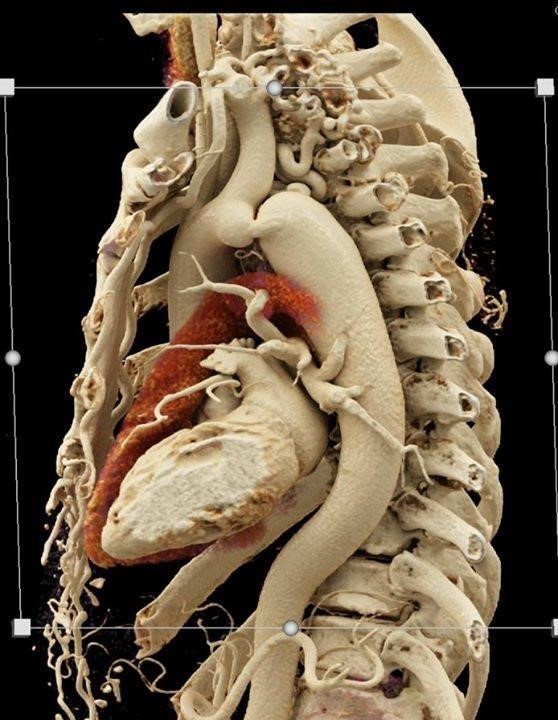

Χειρουργικός σχεδιασμός με βάση την εικόνα

Οι βελτιώσεις στην καρδιακή απεικόνιση συμβάλλουν σημαντικά στο βέλτιστο χειρουργικό σχεδιασμό και μετεγχειρητική παρακολούθηση.

Οι εξελίξεις στην ηχοκαρδιογραφία, την υπολογιστική τομογραφία και την απεικόνιση μαγνητικού συντονισμού (MRI) επιτρέπουν την λεπτομερή μη επεμβατική καρδιολογική εκτίμηση.

Η δισδιάστατη ηχοκαρδιογραφία παραμένει το τυπικό εργαλείο απεικόνισης που χρησιμοποιείται από τους χειρουργούς για την αξιολόγηση της καρδιακής λειτουργίας και των δομικών διαταραχών, όπως η παρουσία ενδοκαρδιακών επικοινωνιών και η ανατομία - παθολογία των βαλβίδων.

Οι εξελίξεις στην τρισδιάστατη ηχοκαρδιογραφία έχουν οδηγήσει σε αυξανόμενη χρησιμότητα αυτών των μοντέλων για τη λειτουργία, σχεδιασμό, την χειρουργική εκπαίδευση, την προσομοίωση και την διεπιστημονική εκπαίδευση.

Επιπλέον, τα 3D-ανακατασκευασμένα μοντέλα και εικόνες είναι πολύτιμα εργαλεία διδασκαλίας.

Η μαγνητική τομογραφία καρδιάς χρησιμοποιείται όλο και περισσότερο στις ΣΚ λόγω υπεροχής στην απεικόνιση χωρίς έκθεση σε ακτινοβολία.

Η μαγνητική τομογραφία είναι ιδιαίτερα χρήσιμη για την ακριβή εκτίμηση μεγέθους και λειτουργίας της δεξιάς καρδιάς και μπορεί να χρησιμοποιηθεί για τη δημιουργία 3D μοντέλων για διεγχειρητική χρήση. Η μαγνητική τομογραφία επιτρέπει υψηλή ανάλυση εικόνων με υψηλή δομική και χρονική ανάλυση πού μπορεί επίσης να χρησιμοποιηθεί για τη μέτρηση των ενδοκαρδιακών ροών.

Ο συνδυασμός ανατομικών δεδομένων και δεδομένων ροής που παρέχονται από την προηγμένη απεικόνιση σε συνδυασμό με προηγμένη προσομοίωση στον υπολογιστή επιτρέπουν την βελτιωμένη χειρουργική προσομοίωση. Τέτοιες προσομοιώσεις μπορεί να διευκολύνουν τον βέλτιστο προεγχειρητικό σχεδιασμό των χειρουργικών επεμβάσεων π.χ βέλτιστη γεωμετρία – αιμοδυναμική σε επέμβαση Fontan. Η μαγνητική τομογραφία συχνά απαιτεί γενική αναισθησία για νεότερους ασθενείς, ιδιαίτερα εκείνους <7 ετών, και ως εκ τούτου, ο κίνδυνος αναισθησίας πρέπει να είναι σταθμίζεται.